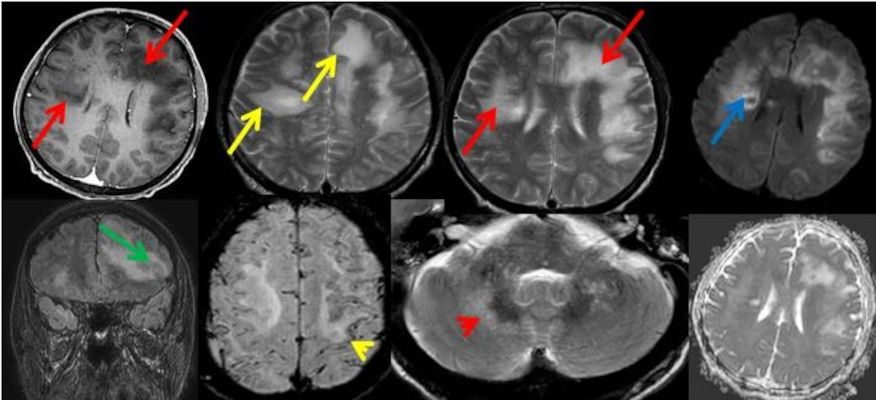

- Bilateral asimetrik subkortikal ve derin beyaz cevherde T1 ağırlıklı görüntülerde belirgin hipointens (oklar), T2A görüntülerde hiperintens (oklar), gri cevhere bakan kesimi düzgün (oklar), DAG’de hiperintens (ok) lezyonlar izlendi. Lezyonlarda T2/FLAIR uyumsuzluğu vardı (ok). Serebellar beyaz cevherde dentat nukleusu koruyan hilal işareti görüldü (ok başı). SWI sekansta sol motor kortekste hipointens kronik glioinflamatuar reaksiyon ile uyumlu sinyal değişikliği izlendi (ok başı).

- Çoğunlukla subkortikal beyaz cevherde ve U fiberlerde, asimetrik, genelde kitle etkisi yapmayan ve kontrastlanmayan demiyelinizan lezyonlar görülür. Korteks ve derin gri cevher tutulumu daha nadirdir.

- PML lezyonları, T1A görüntülerde belirgin hipointenstir. Gri cevhere bakan yüzleri keskin olup T2/FLAIR uyumsuzluğu önemli özelliğidir.

- PML lezyonlarında kronik olarak aktive olan glial hücreler ve mikroglia/makrofajlar sitoplazmalarında yüksek seviyelerde demir ve pigment içerebilir ve SWI da hipointens olarak görülür.

- Kesin bir tanı için, uyumlu klinik ve görüntüleme bulgularına ek olarak JCV için pozitif bir BOS PCR zorunludur.

- Olguda tipik görüntüleme bulgularına ek BOS incelemesinde JCV-PCR pozitif bulundu.